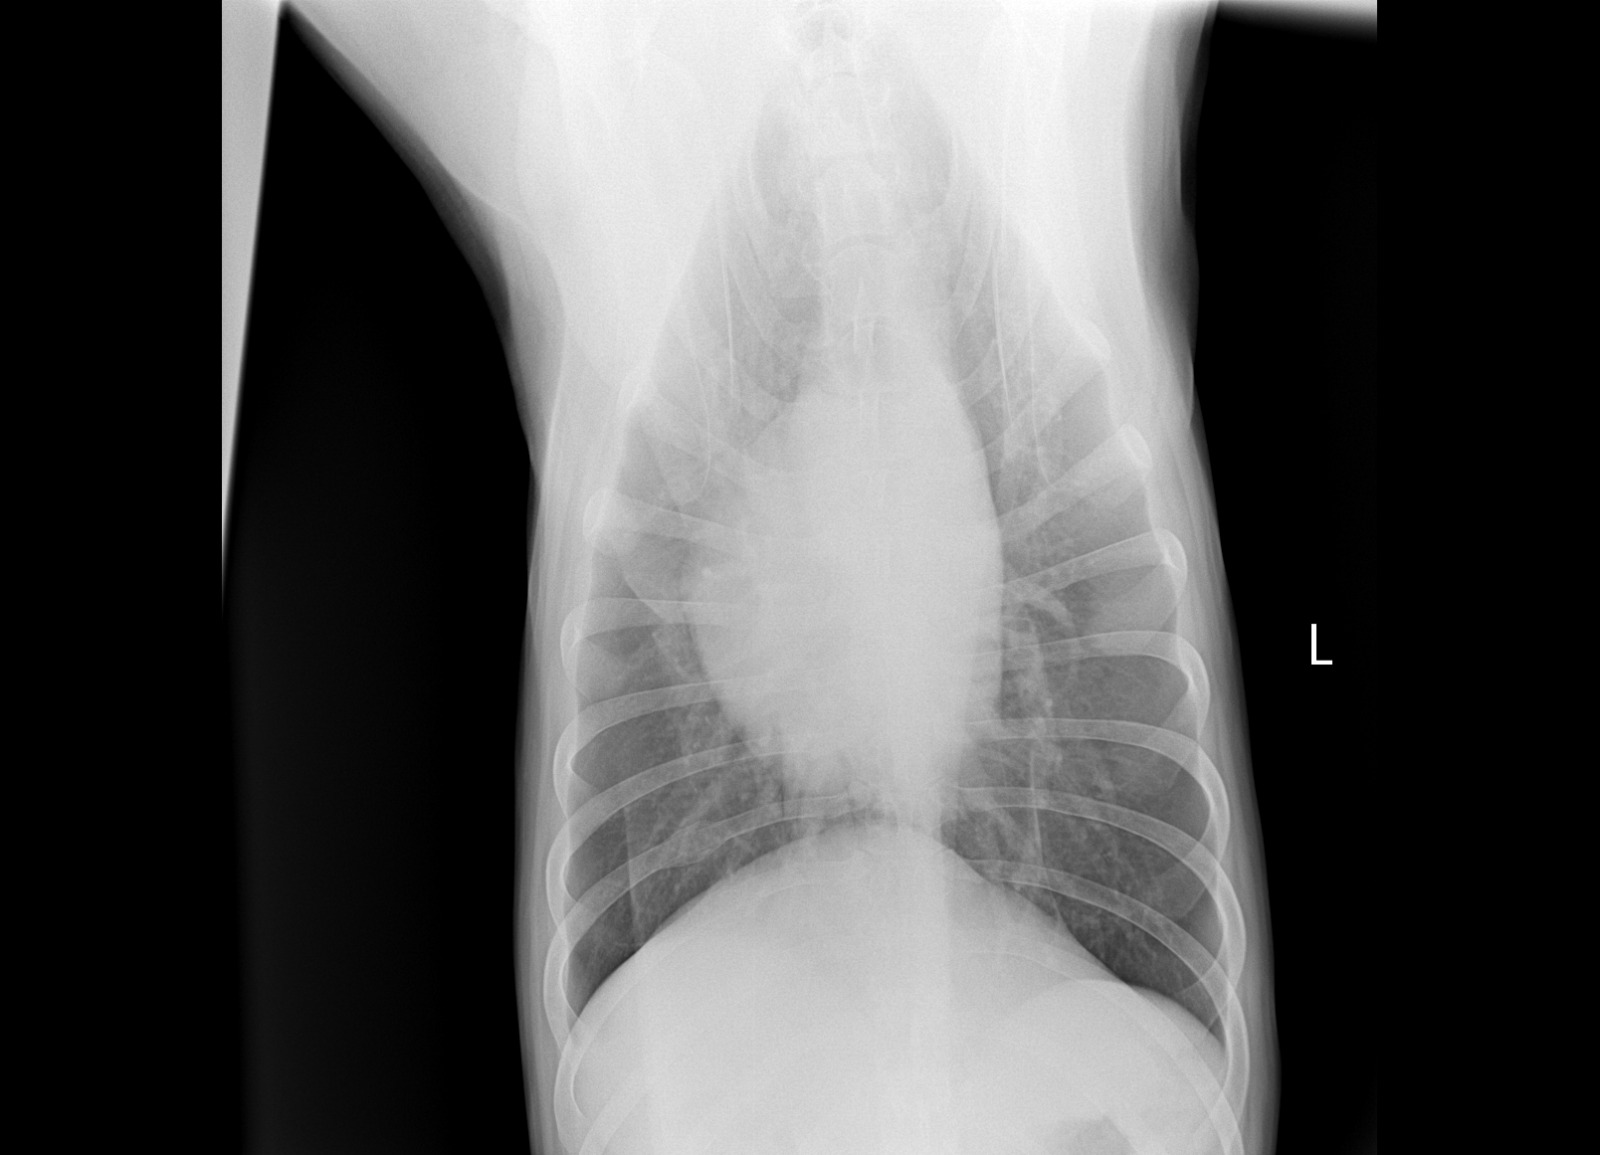

Рентген

Описание рентгена

Интересно, а изменения в бронхах на рентгене от диро или результат хронического бронхита?